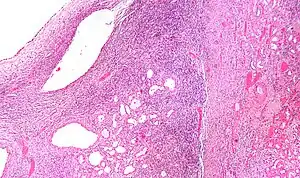

| Micrograph of a cystic nephroma (left of image). Normal kidney is seen on the right. H&E stain. | |